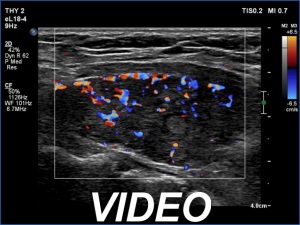

Ultrasonography. Connective tissue replaced the thyroid. Approximately 4 cm above the level of the thyroid, a hypoechoic mass was found. The echo structure was identical to the that of the thyroid seen before the surgery.

Comment. The palpation remains a crucial examination in thyroid patients. If we did not palpate the neck, this lesion would be very likely overlooked on ultrasonography because of the similarity of the echo structure to the neighboring muscle tissue. The two types of tissue differed in two things, the thyroid gland contained less thick and shiny connective tissue bundles, and circulation was detected in it.